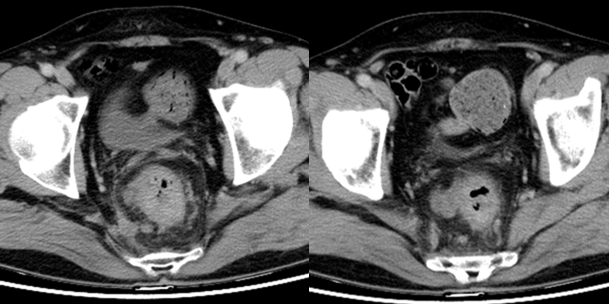

胸腹部CT(2023年7月5日)示:1.直肠中下段癌并周围淋巴结转移,建议内镜检查及MR检查。2.主动脉钙化(图2)。MRI提示直肠癌T3bN2 CRM(+) EMVI(3)。

初步诊断:直肠中低位腺癌(cT3bN2M0)。